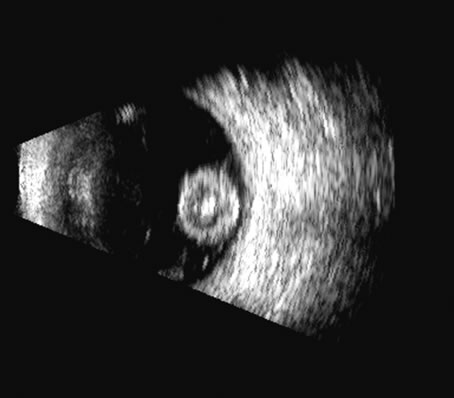

Malignant melanoma varies in its ultrasound presentation from a relatively homogeneous to heterogenous lesion on B-scan. The typical uveal melanoma absorbs sound so that the posterior section is relatively less echoic than the anterior aspect, producing a gradually decreasing amplitude, often to baseline on the A-scan (Fig. 21).

Fig. 21. An ocular tumor at the posterior pole showing the smooth convex border and solid internal reflectants typical of a melanoma.

Melanomas also have varying amounts of melanin, a highly acoustically reflective pigment. As noted, melanomas characteristically show high reflectivity anteriorly, with decreasing reflectance as the sound traverses the tissue. This produces the decreasing amplitude posteriorly in the tumor seen on A-scan and gray-scale B-scan. This effect often enhances the anterior scleral boundary. The posterior tumor border is thus measured as the first “rising” echo from the tumor decline, and it is most easily seen and accurately identified on B-scan.27

Metastatic carcinoma is more heterogeneous, producing a more uniform A-scan amplitude of roughly 50% to 80% of the “scleral” echo amplitude (see below) behind the tumor (Fig. 22). Hemangioma is a very highly reflective tumor with high amplitude all the way through the tumor of 80% to 100% of scleral echo amplitude (Fig. 23).

Fig. 22. Some hemangiomas and metastatic carcinomas may simulate a melanoma. They are differentiated on the basis of a very high amplitude internal echo complex for the hemangioma, a moderately low but sustained echo pattern for the metastasis, and an A-scan with decreasing reflectance as the tumor thickness is traversed. In the center scan of a melanoma, note the double anterior layer caused by edema fluid underlying the crest of the melanoma (arrow).